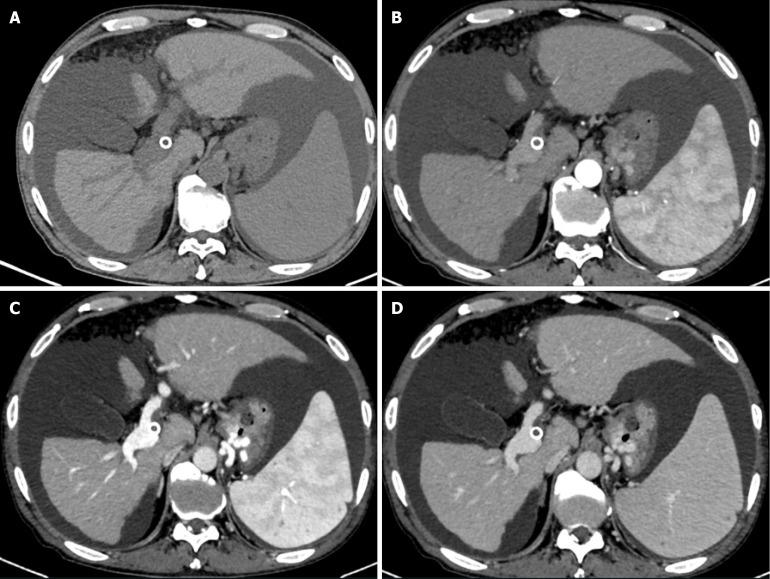

We report a 56-year-old male patient who underwent a TIPS procedure for recurrent melena caused by portal hypertension secondary to hepatitis B and experienced a stent fracture 15 months post-procedure. He was readmitted 30 months after the initial TIPS due to recurrent esophagogastric variceal bleeding and ascites. An attempt to revise the dysfunctional shunt a stent-in-stent approach was unsuccessful. Consequently, a parallel TIPS procedure was successfully performed the proximal end of the fractured stent to decompress the portal venous system. At the 1-month follow-up, the patient exhibited no recurrent variceal bleeding, and his ascites had significantly decreased. Twelve-month postoperative monitoring revealed no hepatic encephalopathy and no recurrence of bleeding or ascites. Additionally, we review the existing literature on post-TIPS stent fractures to explore the underlying mechanisms contributing to this complication.

我们报告一名56岁男性患者,因乙型肝炎继发门静脉高压导致反复黑便而接受了TIPS手术,并在术后15个月发生了支架断裂。由于反复出现食管胃静脉曲张出血和腹水,该患者在初次TIPS术后30个月再次入院。尝试采用支架内支架方法修复功能失调的分流未成功。因此,在断裂支架的近端成功实施了平行TIPS手术,以减压门静脉系统。在1个月的随访中,患者未出现静脉曲张再出血,腹水明显减少。术后12个月的监测显示无肝性脑病,出血或腹水未复发。此外,我们回顾了关于TIPS术后支架断裂的现有文献,以探讨导致这一并发症的潜在机制。